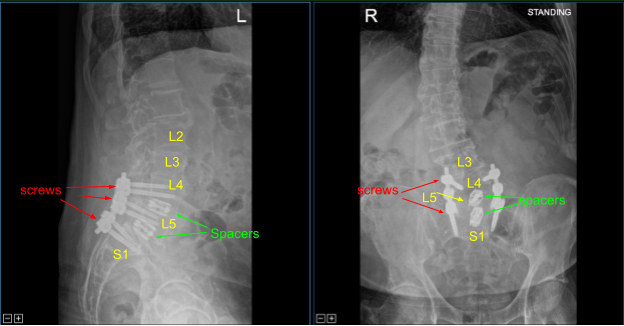

Expandable titanium interbody spacers, 15-degree lordotic at L5-S1 and 10-degree lordotic at L4-5, were placed under fluoroscopic guidance and expanded to proper fit. There was partial subsidence of the interbody spacer at L5-S1 into the L5 body, but it was secured and tight fit and imaging showed midline positioning.

CT scan was then obtained (shown above) which showed correct positioning of all the hardware. Neuromonitoring signals were stable. The wound was irrigated copiously. Bilateral transverse processes were decorticated for posterolateral arthrodesis from L4 to S1.

Precut titanium rods were contoured with rod benders and placed across the screw tulips from L4 to S1and secured with locking caps which were all final tightened with a torque and anti torque device. Final AP and lateral x-rays showed correct and complete hardware implantation.

Post Op X-ray